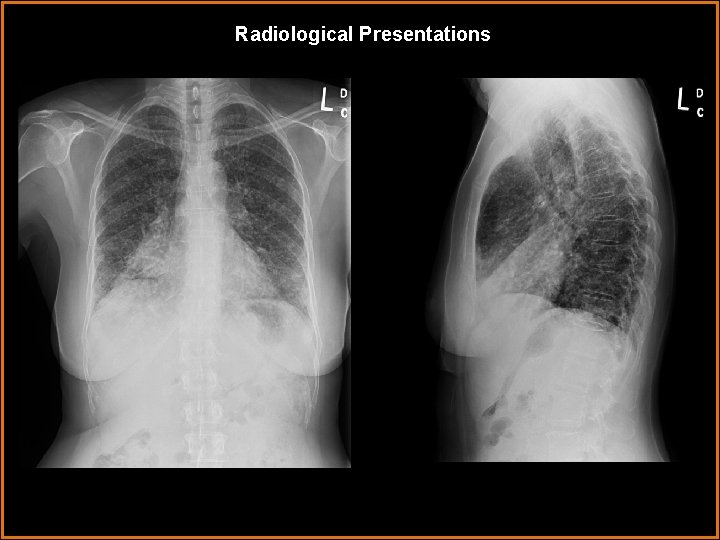

Findings and Differentials Findings: PA and lateral radiographs demonstrate innumerable small nodules in a miliary pattern. Also, increased opacity in the right base obscures the heart border with depression of the minor fissure. The lateral image confirms right middle lobe atelectasis. CT imaging through the lung bases confirms milary nodules in the lung and atelectasis of the right middle lobe. The abdominal image reveals bilateral adrenal masses and subcutaneous lesions. Differentials: • Metastases • Miliary infection